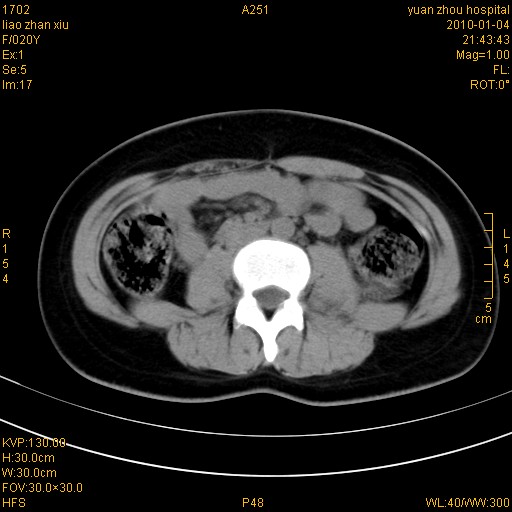

标题: CT23985:F20Y 外伤典型病例 [打印本页]

标题: CT23985:F20Y 外伤典型病例

左肾挫伤,包膜下积血,l3、4左侧横突多发骨折。

双侧肾胞膜下出血,左侧较多。l3、4左侧横突多发骨折。

2、l3、4左侧横突多发骨折;

左肾挫伤,包膜下积血,l3、4左侧横突多发骨折

气死我了,明明l1、2,为什么都说3、4.

左肾挫伤,包膜下积血,L1、2、3、4左侧横突多发骨折。